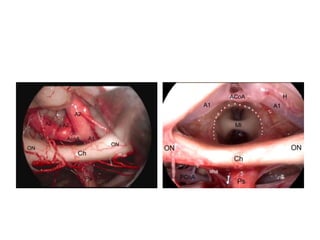

Right supraorbital approach (0 optic). 1 Diaphragma sellae, 2 cn II, 3 optic

tract, 4 ICA, 5 A1, 6 M1, 7 C. N.III, 8 anterior petroclinoid fold, 9 anterior

clinoid process.

A Optocarotid window,

B window between ICA and cn III –I think B

is nothing but posterior clinoid process

C window lateral of cn III

Right supraorbital approach (30 optic).

Window between ICA and cn III : 1

tuber cinereum, 2 left P1, 3 left cn III, 4

BA, 5 right P1, 6 right SCA, 7 right cn III

Window between cn II and ICA: 1 left

PCoA, 2 left P2, 3 left cn III, 4 left P1, 5

left SCA, 6 BA, 7 doubled right SCA, 8

right cn III, 9 right P1, 10 mammillary

bodies, 11 tuber cinereum, 12 right

PCoA, 13 right M1.* sucker